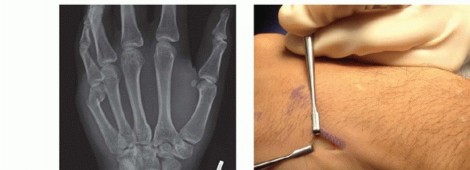

TRANSVERSE PINNING

TECH FIG 2 • A. Angled metacarpal neck fracture. B. Incision at the ulnar base of the fifth metacarpal, exposing the insertion of the extensor carpi ulnaris (ECU) on the base of the metacarpal. Incision located on ulnar aspect of metacarpal to minimize irritation of the extensor tendons. C. Unicortical tunnel at the base of the metacarpal. D. Sample of prebent pin. Tip is angled to facilitate passage through the shaft. E. In metacarpal neck fractures or those at risk of shortening, it is important to bring the pins to the subchondral bone of the metacarpal head but not violate the head.